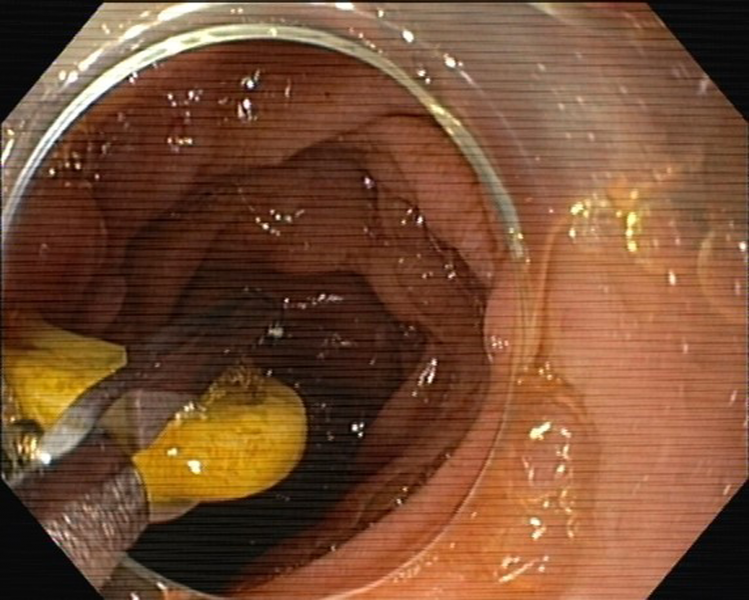

Bone stuck in diverticular ostia of the sigmoid colon: an endoscopic challenge

Fotografia